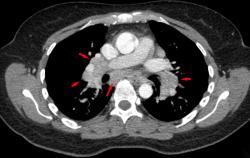

由于结节病,CT扫描呈现出纵隔淋巴结的肿大(箭头所示)

中华人民共和国的医学资料中将X线的改变分为五期,以Ⅰ期和Ⅱ期较为常见:

Ⅰ期:两侧肺门和/或纵隔淋巴结肿大,右主支气管旁淋巴结常常伴有肿大,而肺内无明显异常。

Ⅱ期:肺门淋巴结的肿大,伴肺浸润影。

Ⅲ期:可见肺部浸润影,并无肺门淋巴结肿大。

Ⅳ期:肺内发生纤维化、肺大疱和肺囊肿等改变。

以上分类仅仅是相对而言的,并不能说明一定会有0期-Ⅳ期的病变,可以是跳跃式发展。CT扫描(尤其是HRCT)能够更准确地估计结节病的类型、肺间质的病变程度与淋巴结的肿大情况。